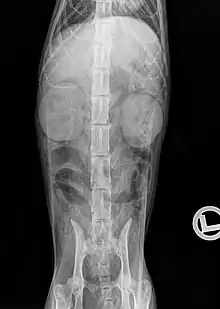

Radiographie

Un examen radiographique peut permettre de détecter des modifications de taille, d'opacité et de position des reins, et mettre en évidence certaines urolithiases : les calculs de struvite sont parfois visibles (phosphate de magnésium et d'ammonium) et les calculs d'oxalate de calcium sont opaques aux rayons X. Des minéralisations des tissus mous peuvent également être observées autre part, notamment en région sous-pleurale. Chez les chats fortement amaigris, ou dans le cas d'épanchement liquidien dans l'espace rétropérinéal, le contraste abdominal peut être diminué. L'urographie intraveineuse peut permettre de visualiser les voies urinaires, par injection d'un produit de contraste (p. ex. iopamidol ou iohexol) dans la circulation sanguine, qui est ensuite excrété par le rein. Cet examen est indiqué notamment pour la recherche d'une obstruction des voies urinaires, par des urolithiases par exemple, et de visualiser une éventuelle distension de la cavité pyélique qui en résulte (hydronéphrose)[27].